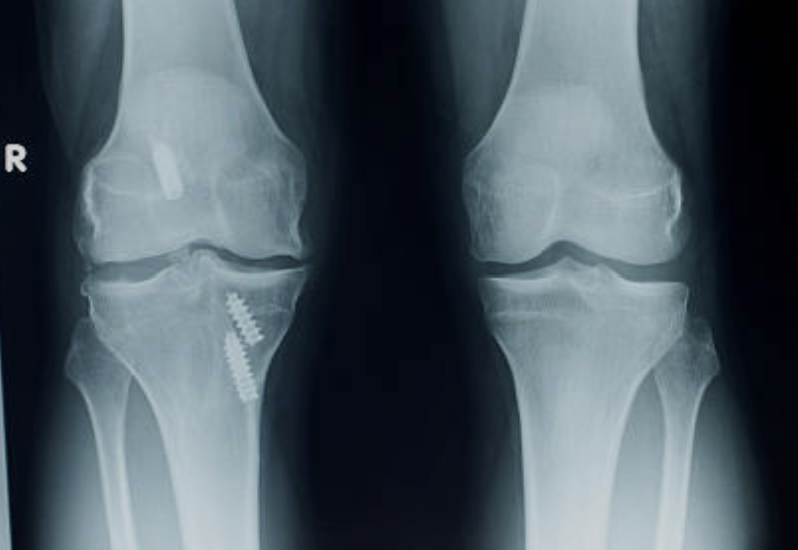

수술적 치료는 손상된 인대가 완전히 파열되거나, 환자가 젊고 활동적이며 스포츠나 격렬한 운동을 하고 싶은 경우에 적용됩니다. 수술적 치료의 목표는 손상된 인대를 제거하고 새로운 인대로 대체하여 무릎 관절의 안정성과 기능을 회복시키는 것입니다. 수술적 치료에는 다음과 같은 방법들이 있습니다 .

- 봉합술: 파열된 범위를 꿰메 주는 수술입니다. 파열의 형태에 따라 전방십자인대 견열 골절이거나 인대 부착 부 파열의 경우 봉합술을 할 수 있습니다.

- 재건술: 새로운 인대로 만들어 주는 수술입니다. 자신의 힘줄을 사용하거나 다른 사람의 힘줄을 사용하는 방식으로 진행됩니다. 관절내시경과 최소 침습 기법을 사용하여 수술 부위의 손상과 회복 기간을 줄일 수 있습니다.